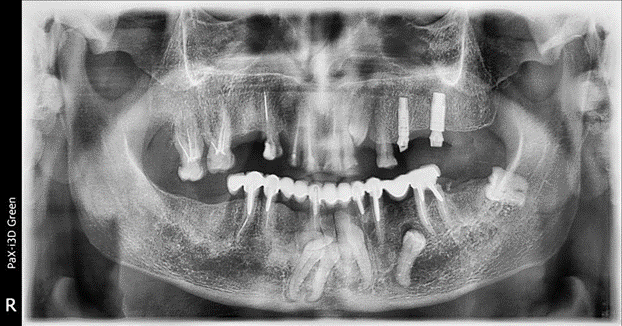

Теперь ещё несколько редких и странных случаев. Например, пациент с девятым зубом. Сейчас восьмёрки-то не у всех есть, а он где-то нашёл сверхкомплектный. Но начнём мы с другого пациента, у которого до старости зубы остались внутри челюсти, вот:

Зубы внутри челюсти

Вот ещё раз картинка:

Это довольно печальный случай пожилого пациента. Внизу в челюсти (да и слева — буква R означает правую сторону челюсти с точки зрения пациента) вы можете увидеть непрорезавшиеся зубы.

Сверху временные, то есть молочные зубы, снизу постоянные. Вот подробный пост, как это устроено и какие особенности лечения детей вызывает. Здесь важно то, что пациент в возрасте около 60 лет всё ещё имеет несколько непрорезавшихся зубов.

Увы, они не прорежутся никогда.

Пациент из региона, в молодости денег на поездку в Москву или Европу для лечения у него, очевидно, не было, да и про достижения науки там вряд ли знали достаточно. Советский врач на месте сделал лучшее из возможного: когда молочные зубы износились, поставил сначала какую-то временную конструкцию, а потом, позже, когда пациент дорос до своего номинального размера, установил постоянную большую мостовидную конструкцию, которую вы тоже видите.

Тем не менее, когда зубы есть (а у пациента они в детстве были почти в комплекте), их можно попробовать вытащить наружу, прикладывая долгое механическое усилие. То есть мы бы вкрутили маленькие винты в кости выше и начали бы тянуть несколько месяцев.

Сейчас тянуть зубы бесполезно, они давно уже живут в толще челюсти. Тем не менее вмешательство всё же нужно. Мост кончается. На таких больших конструкциях часто страдает точность. Слева в заднем отделе конструкция потеряла геометрию, там не было хорошей посадки — и образовался рецидив кариеса под металлом. Можно было санировать очаг и снова вернуть всё как было, но пациент хотел комфорта на всю оставшуюся жизнь. Поэтому протезирование. То есть мы вместо одной большой конструкции поставили несколько поменьше независимых, что в перспективе означает очень высокую точность и совершенно другие нагрузки. Вот рассказ про эту разницу, он вам пригодится, если ваши родители потеряют зубы.

Причины генетические. Увы, корни сформированы, но не прорезались. Называется такое явление полной ретенцией. Ещё бывает вариант, когда пациент рождается без второго комплекта зубов вообще. Тогда они не выпадают, так как им не на что сменяться, нечему прорезываться. Они поражаются кариесом и осложнениями, стираются и изнашиваются, как менее крепкие. В любом случае решения сейчас есть, и они функционально и эстетически близки к норме (если не считать отсутствие чувствительности на имплантатах).

Пациенту мы поставили протезы, всё прошло хорошо, он теперь может радостно жевать стейк. А может не жевать. Главное — такой выбор есть.